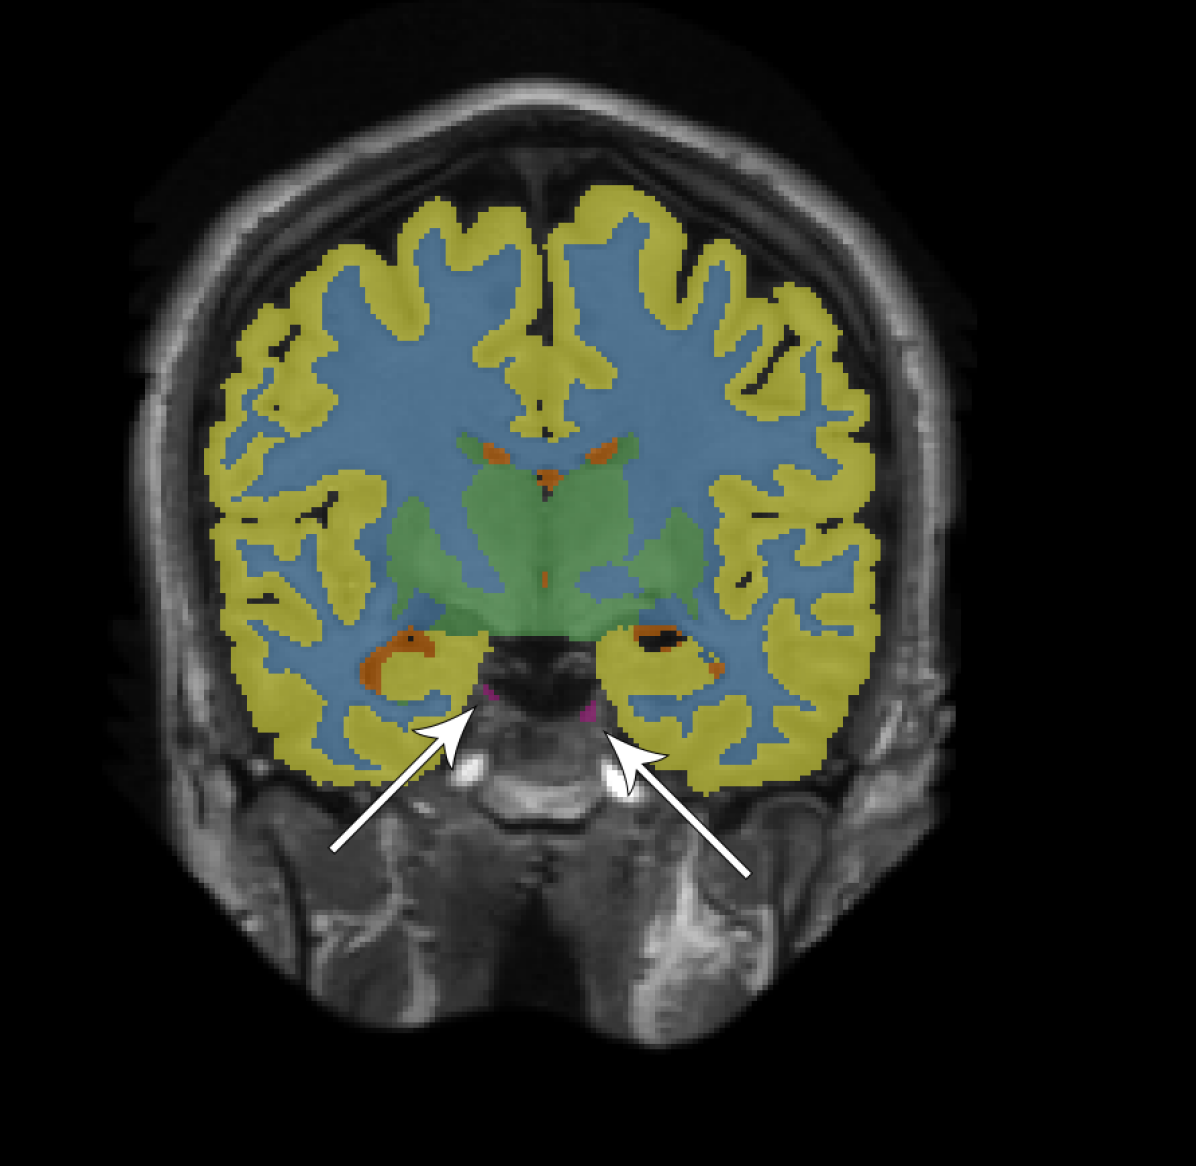

Figure 2 provides a visual comparison between the segmentations obtained with and without adversarial training, showing that the adversarial approach generally resulted in less noisy segmentations. The same can be seen from the total number of 3D components (including the background class) that compose the segmentations. For the adult subjects, the number of components per image () decreased from to using the fully convolutional network and from to using the dilated network. For the elderly subjects, the number of components per image () decreased from to using the fully convolutional network and from to using the dilated network.

We have presented an approach to improve brain MRI segmentation by adversarial training. The results showed improved segmentation performance both qualitatively (Figure 2) and quantitatively in terms of DC (Figure 3). The improvements were especially clear for the deeper, more difficult to train, fully convolutional networks as compared with the more shallow dilated networks. Furthermore, the approach improved structural consistency, e.g. visible from the reduced number of components in the segmentations. Because these improvements were usually small in size, their effect on the DC was limited.